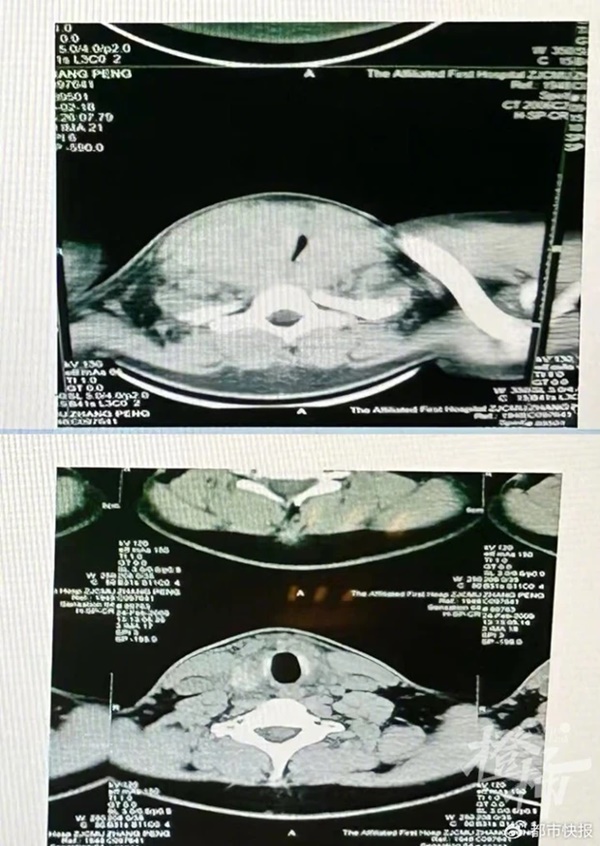

Qua kiểm tra siêu âm tuyến giáp, đường thở của Tiểu Vũ đã bị khối u tuyến giáp chèn ép nghiêm trọng, gây khó khăn khi hô hấp và tiếng ngáy lớn. Giáo sư Phó cho biết, sau khi phẫu thuật, Tiểu Vũ hiện đã có thể thở lại một cách bình thường và nhẹ nhàng.

Hình ảnh đường thở của Tiểu Vũ trước và sau khi phẫu thuật (Hình ảnh bệnh viện cung cấp)